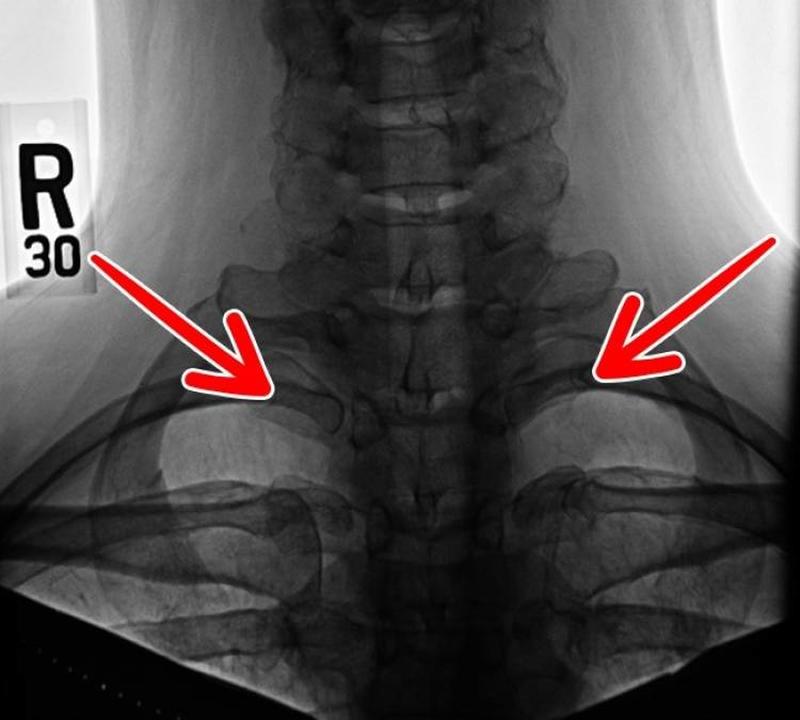

The Neck Rib

There is a set of cervical ribs (meaning in the neck area) that is a leftover from the age when reptiles ruled supreme. These ribs appear in less than 1% of the human population, however, they can cause problems for those that have them.